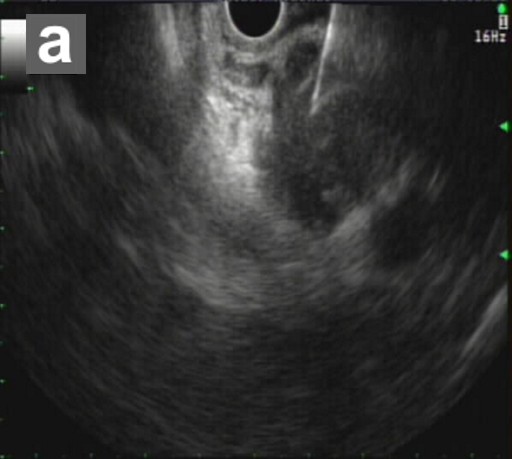

The patient remained clinically stable for 3 years without any overt gastrointestinal or constitutional symptoms. Because the CA 19-9 continued to fluctuate, and because of the patient’s concerns that the pancreatic cysts may become malignant, a very rigorous surveillance program was carried out with two ERCPs (2003 and 2004), three EUSs (2003, 2004, and 2006), three CTs (2003, 2004, and 2006) and five MRCPs (2003, 2004, 2005, 2006, and 2008) (Figure 3). The main pancreatic duct was not dilated on any of the examinations. The subcentimeter cyst was present in the head of the pancreas, which were unchanged compared to imaging studies from 2003 to 2008. However, in 2009, an MRCP revealed a 2 cm solid mass in the pancreatic head, adjacent to the cyst and compressing common bile and pancreatic ducts (Figure 4). Immunochemical findings of the fine-needle aspiration (FNA) specimen were diagnostic for ductal adenocarcinoma (Figure 5). Because of unresolving Lady Windermere syndrome, patient age, and patient preference, chemotherapy would be more appropriate than surgery. The patient received one cycle of gemcitabine and developed respiratory distress with atrial fibrillation, resulting in prolonged hospitalization. Eventually, the patient expired from respiratory failure.

Figure 5. EUS-FNA (a.) of pancreatic ductal adenocarcinoma. Immunohistochemical staining of the FNA specimen (b.) for cytokeratins, AE1:AE3 (Ventana, Tucson, AZ, USA; predilute), and CAM5.2 (Becton Dickinson, San Jose, CA, USA; diluted 1:1) shows strong reactivity of the malignant epithelial cells infiltrating a desmoplastic stroma. Both stains are performed on BenchmarkXT® (Ventana, Tucson, AZ, USA) stainer with ultraView® (Ventana, Tucson, AZ, USA) multimer detection system. |